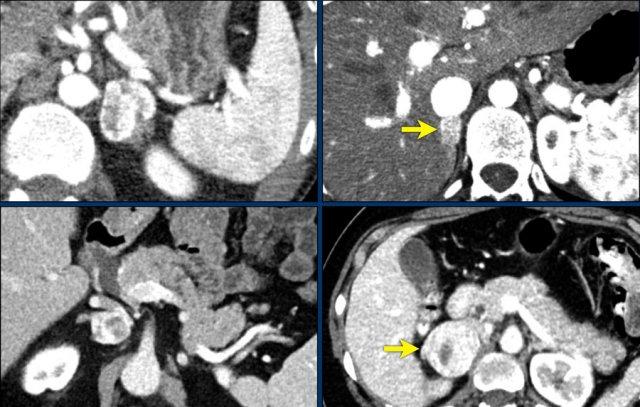

Các hình ảnh cho thấy u tình cờ tuyến thượng thận hai bên được phát hiện ở bệnh nhân 64 tuổi được chụp CT để phân tích phình động mạch chủ bụng.

Hình chụp pha động mạch cho thấy các tổn thương hai bên với tỷ trọng 50 HU.

Trên CT không tiêm thuốc thực hiện vài ngày sau, tỷ trọng ở cả hai tuyến thượng thận đều dưới 10 HU, xác nhận đây là các u tuyến giàu lipid.